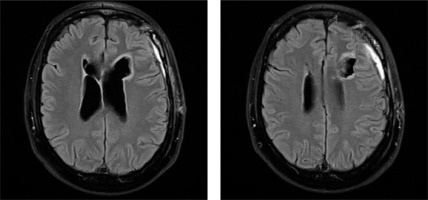

An MRI scan showed an irregular mass in the frontal horn of the left lateral ventricle and a nodular lesion with a cystic appearance in the frontal horn of the right lateral ventricle (Figure I). The maximum size of the cysts was approximately 46 mm, with a solid portion of 43 mm. The tumor was hyperintense with variable contrast enhancement. The tumor mass was shown to compress the foramen of Monro, resulting in an enlargement of the lateral ventricles.

Figure I

Subependymoma. Preoperative MRI image showing an intraventricular tumor arising from the ventricular wall. Axial post-contrast T1 imaging